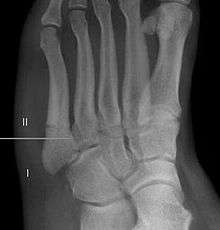

A legitimate concern in any fracture is whether the fracture will heal quickly and without complication. Failure of the fractured ends to unite is called non-union and its frequency varies with the fracture site, some fracture sites being notorious for non-union. An example of such would be a scaphoid (navicular) fracture of the wrist. Such a complication also involves fractures of the proximal end of the fifth metatarsal, such as the Jones fracture. This has been the subject of interest, and initially led to the description of three zones at the proximal end of the fifth metatarsal.

Zones I and II have been associated with relatively guaranteed union and this union has taken place with only limited restriction of activity combined with early immobilization. On the other hand, zone III has been associated with either delayed or non-union and, consequently, it has been generally agreed that fractures in this area should be considered for some form of internal immobilization, such as internal screw fixation. More recently, because of the similar behavior of the original zones I and II, it has been suggested that zones I and II be combined leading to current recommendations for two zones, zone I being associated with uncomplicated union, and zone II being prone to nonunion and therefore considered for internal fixation.

These zones can be identified anatomically and on x-ray adding to the clinical usefulness of this classification.[3] It should be emphasized that surgical intervention is not, by itself, a guarantee of cure and has its own complication rate. Other reviews of the literature have concluded that conservative, non-operative, treatment is an acceptable option for the non-athlete.[4]

Other proximal fifth metatarsal fractures

Other proximal fifth metatarsal fractures exist, although they are not as severe as a Jones fracture. If the fracture enters the intermetatarsal joint, it is a Jones fracture. If, however, it enters the tarsometatarsal joint, then it is an avulsion fracture caused by pull from the peroneus brevis. An avulsion fracture is sometimes called a Pseudo-Jones fracture or a Dancer's fracture.